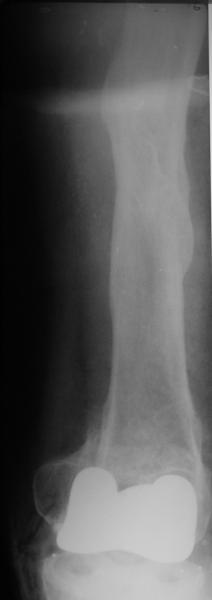

Глубокоуважаемые коллеги, Мужчина 41 года поступил с повторным (предыдущий в 2001 г.) переломом (3-недельной давности) над протезом коленного сустава.

В 1994 множественная травма, в том числе открытый перелом надколенника, осложнившийся гнойным артритом, и на этой же стороне перелом диафиза бедра (лечили в аппарате). В 1998 г. выполнено эндопротезирование коленного сустава.Предыдущий перелом (3 года назад) лечили консервативно, сросся при неустраненном смещении дистального блока бедра кзади ~ на 1 см.Амплитуда движений в коленном суставе перед последним переломом была ~90 градусов. Ходил без дополнительной опоры.Снимки в приложении. Какие будут предложения по поводу оперативного лечения в нынешней ситуации? У нас споры между ретро- и антеградным закрытым интрамедуллярным остеосинтезом.

A male 41 years old transferred to our unit with 3 week old femoral fracture near the knee prosthesis after a mimimal fall. In 1994 he sustained multiple injury with open patella fracture (complicated with septic arthritis), and ipsilateral femoral shaft fracture treated by ex-fix. TKA performed in 1998. In 2001 he got a periprosthetic fracture which was treated nonoperatively and healed with ~1 cm dorsal displacement of the distal femoral block. Knee ROM prior the recent injury was about 90-95 degrees. He didn't use walking aid.Images attached. I request your suggestions regarding surgical options in the situation? We mostly discuss ante- vs retrograde closed nailing.